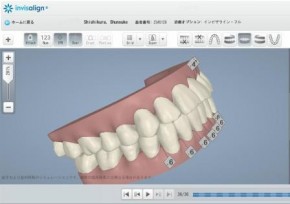

1日目(60分)・・・(虫歯・歯周病)基本検査・写真・型取り・レントゲン・セファロ分析・3Dシュミレーション→マウスピース完成

歯型から3Dシミュレーションへ

30~100個(個人差)の徐々に変化しているマウスピースを1~2週間ごとに新しいマウスピースに交換します。